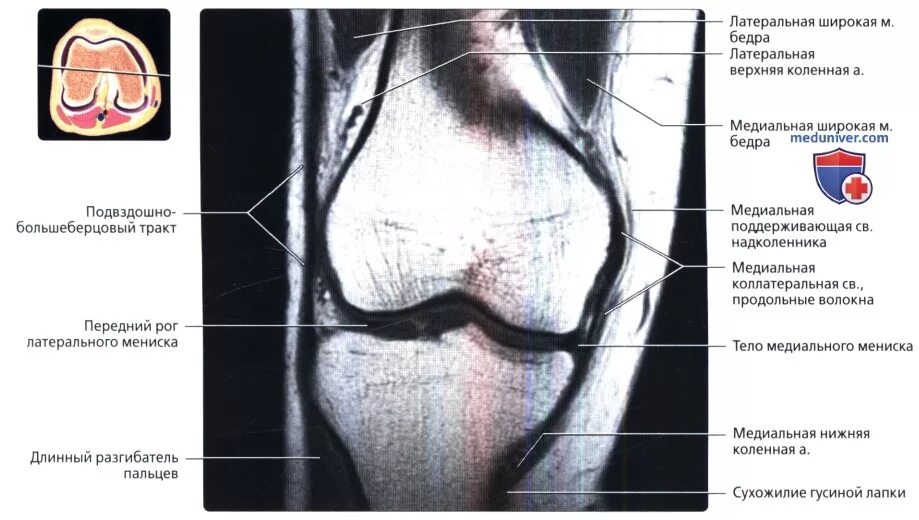

Вывих надколенника код мкб 10